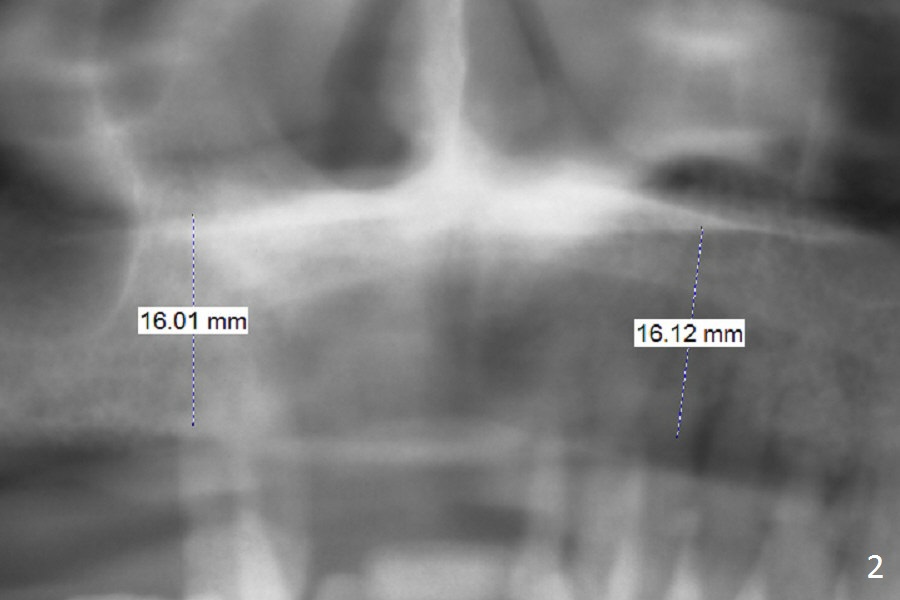

A 65-year-old woman has an upper partial denture and 3 mobile teeth (Fig.1 : #5,12,13). She wants to keep the RPD. The loose teeth are replaced by implants. There is enough bone height (Fig.2). Initial osteotomy depth will be 14 mm. Insert parallel pin(s) and take PA.